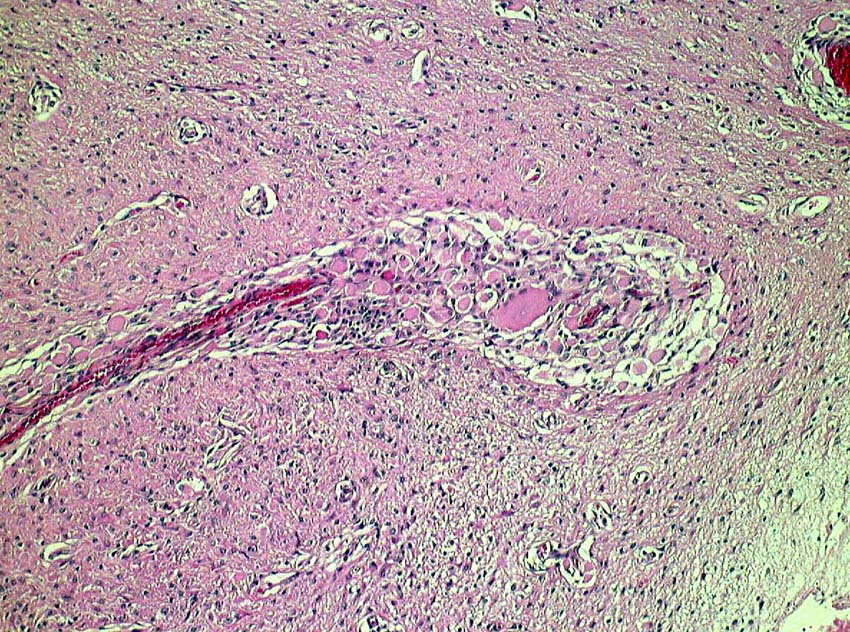

LCHの病理像

頭蓋骨のLCHの病理像です。左はHE染色,右はランゲルハンス細胞に特異性の高いCD1a(specific to dendric Langerhans cells) 染色です。多数のLangerhans cellとともに,組織球,リンパ球,好酸球,多核細胞など多彩な細胞浸潤があります。これは活動性のLCHの病巣から摘出したものです。

自然緩解して収まった病巣を生検術で摘出しても,このような典型的な病理像がなくて慢性炎症像がみられるだけのことがあります。その場合は確定診断がつきません。

左は,活動性の病巣です。右は,活動期が終わり慢性炎症所見を伴いながら肉芽種に移行する過程です。

別な例の病理像です

左はHEで血管周囲に多様な細胞浸潤像があります,右はS-100です

CDa-1染色です